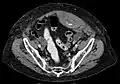

Rectus sheath hematoma seen on axial CT โ with active bleeding under Marcoumar- Rectus sheath hematoma as seen on ultrasound[2]